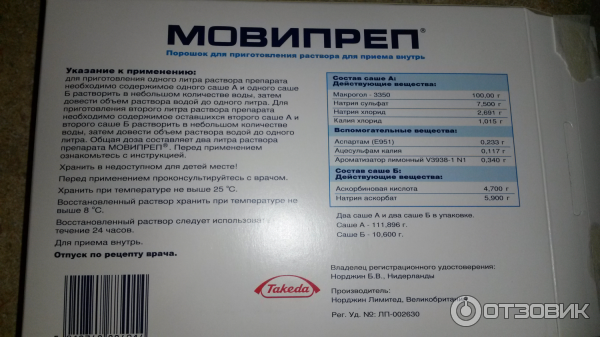

Подготовка к ирригоскопии: необходимые препараты